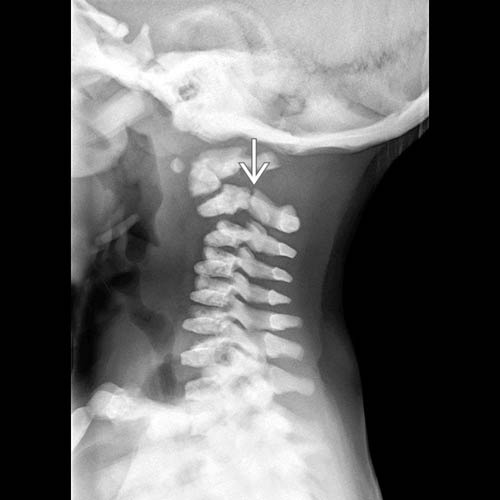

Brittle Bone Disease, Xray Stock Image C036/5861 Science Photo Brittle Bone Disease Radiology A child born with oi may have soft bones that fracture easily, bones that. Osteogenesis imperfecta (oi), commonly called brittle bone disease, is a genetic disorder characterised by increased. Osteogenesis imperfecta (oi), also known as brittle bone disease, is a rare genetic multisystem disorder of type i collagen. It is also called brittle. Osteogenesis imperfecta (oi), commonly called “brittle bone. Brittle Bone Disease Radiology.